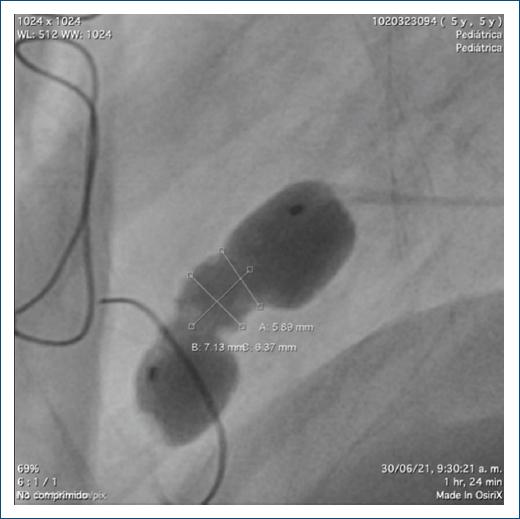

Se trata de un paciente remitido a una institución de alto nivel de complejidad en la ciudad de Medellín, Antioquia, Colombia, a los 20 días de vida, producto de un embarazo a término, con adaptación neonatal espontánea, peso y talla adecuados para la edad gestacional, con paraclínicos infecciosos normales y diagnóstico prenatal de aneurisma ventricular izquierdo (AVI) de 1.6 mm de diámetro, confirmado por ecocardiografía y RM cardiaca posnatal, con ausencia de endocardio asociado, hipocinesia grave, con función ventricular normal y extrasistolia ventricular leve, unifocal, bigeminada, con una carga arrítmica total no significativa del 0.6%. El caso fue llevado a reunión médico-quirúrgica, en la que se decidió realizar un cateterismo diagnóstico, el cual mostró arterias coronarias normales, con divertículo del ventrículo izquierdo (DVI) gigante (Fig. 1).

Figura 1 A: ventriculografía que muestra un aneurisma en el ápex cardiaco. B: vista lateral del aneurisma.